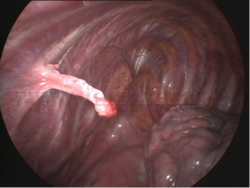

Malformaciones costales